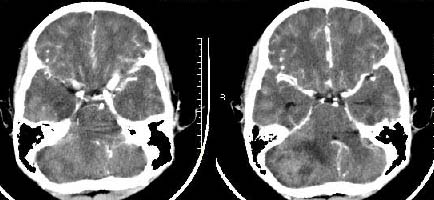

以下是引用子期在2009-6-10 21:34:00的发言:[br]髓母细胞瘤一般位于中线附近和小脑蚓部,该病灶位于右侧小脑半球,倾向于毛细胞型星形细胞瘤,当然也不能完全排除髓母细胞瘤。

以下是引用随光逐影在2009-6-10 22:26:00的发言:[br]考虑右侧小脑胶质瘤,髓母细胞瘤待排。

以下是引用影象小泰斗在2009-6-10 22:14:00的发言:[br]年龄及影像表现军符合小脑星形细胞瘤表现![br]期待病理结果!